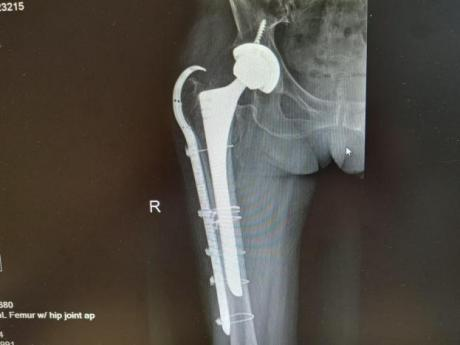

2025年11月1日,由遵义市医学会手外科分会主办、遵义市第二城市医疗集团(贵州航天医院)承办的遵义市医学会手外科分会学术交流会暨贵州省继续医学教育项目《急诊手外伤治疗临床研究新进展专题研讨班》在贵州航天医院成功举办,汇聚了遵义市手外科领域专家及基层医疗骨干,通过专题研讨与临床经验分享,共探急诊手外伤诊疗新进展。 会议特邀遵义市医学会手外科分会主任委员金文虎教授,遵义市医学会手外科分会副主任委员张子阳教授,遵义市医学会手外科分会常务委员杨绍浦教授,贵州航天医院陈明勇教授、赵兴东教授等遵义市手外伤专家进行交流分享;贵州航天医院党委委员、副院长彭亮参加会议并致辞,贵州航天医院骨科医务人员,遵义市第二城市医疗集团成员单位及红花岗区、绥阳县、桐梓县等区县医疗机构手外伤骨干参与。 贵州航天医院党委委员、副院长彭亮致辞 学术交流 本次学术交流以“急诊手外伤治疗临床研究新进展”为主题,通过理论授课与临床案例结合,共同探讨急诊手外伤临床诊疗全链条诊疗策略、关键技术、临床研究新进展,促进规范化诊疗技术向基层下沉,助力提升区域手外伤应急处置与修复能力。 贵州航天医院赵兴东教授分享《急诊手外伤的诊断与治疗原则》 贵州航天医院陈明勇教授分享《开放性骨折的治疗原则》 贵州航天医院张军教授分享《甲沟炎Winograd手术的临床应用》 贵州航天医院赵兴东教授分享《手部常见的皮肤缺损及治疗原则》 贵州航天医院张艳金教授分享《开放性骨折的清创术》 贵州航天医院冷家雄教授分享《下肢创面修复的常用皮瓣之股前外侧皮瓣》 贵州航天医院邬夏荣教授分享《踝关节慢性不稳的诊治》 贵州航天医院卢懿明教授分享《掌骨骨折》 贵州航天医院张艳金教授分享《手部肌腱的解剖与修复方法》 本次研讨班为遵义市手外科领域医务人员提供了深度交流契机,强化了医疗机构间的协作网络,进一步推动学科创新与临床实践融合,为健康遵义建设注入新动能。 贵州航天医院骨科专家简介 陈明勇 骨一科主任,副主任医师 临床擅长:从事创伤骨科工作约20年,对骨缺损、骨不连、骨肿瘤、肢体畸形等的肢体矫形重建及功能重建,慢性化脓性骨髓炎的根治治疗、糖尿病足的保肢治疗、快速康复理念(ERAS)下的老年骨折的诊治,四肢复杂骨折的诊治,四肢骨折等微创手术治疗具有丰富的临床经验。 2004年毕业于遵义医学院临床专业,曾在中国人民解放军总医院、广西医科大学第一附属医院、上海第六人民医院骨科进修。中国中西医结合学会骨伤科专业委员会横向骨搬移治疗糖尿病足及微血管网再生学组首届委员,遵义市医学会创伤分会常务委员。 瞿 晖 骨科党支部书记,骨二科主任,副主任医师 临床擅长:对骨科的常见病、关节外科、脊柱外科及运动医学疾病的诊治具有丰富的临床经验,熟练掌握骨科手术操作技术。 毕业于遵义医学院临床医学系,2005年前往广州中山大学第一附院骨显微医学部进修学习,2011年前往成都华西医院进修学习,并多次在省内外学习骨科相关知识,是中华医学会骨科分会会员。 赵小锋 中共党员,骨二科副主任,副主任医师 临床擅长:从事骨科临床工作11年,对骨科常见病、多发病诊疗有较为丰富的临床经验,擅长脊柱相关疾病诊断及治疗,尤其是颈、腰、腿疼痛疾病诊断及治疗,擅长胸腰椎骨折微创经皮穿刺内固定术、经皮穿刺椎体成形术、经皮穿刺脊柱内镜下腰椎间盘摘除术、单纯开创腰椎间盘摘除术、腰椎滑脱复位椎间植骨椎融合内固定术、腰椎管狭窄减压融合内固定术及人工髋、膝关节置换术等。 2012年毕业于遵义医学院外科学专业硕士研究生,2019年参加“遵义市115医学人才精英计划”于上海交通大学第一附属医院培训学习,2023年于北京大学第三人民医院脊柱外科进修学习,曾获得遵义市优秀医师荣誉称号。 遵义市手外科第一届委员,遵义市医学会创伤分会第一届委员,遵义市医学会创伤分会第二届委员,贵州省康复医学会第三届脊柱脊髓专业会委员,遵义市医学会烧伤与整形外科学分会委员,发表论文5篇,其中国家级核心期刊1篇,SCI论文1篇,主持市级课题1项并结题,参与市级课题2项。 赵兴东 骨科主任医师 临床擅长:擅长骨科的常见病及各种创伤、四肢骨折创伤修复、骨感染、手足疾病的诊治和手足体表畸形的矫形整复,熟练掌握骨科四肢骨病及创伤的手术操作技术,尤其在四肢关节复杂性损伤、手足外伤、组织缺损创面、难治创面的皮瓣修复方面及平足、高弓足矫形方面及四肢慢性疼痛诊治、康复方面具有丰富的临床经验。 硕士研究生,毕业于遵义医学院临床外科系,2015年前往山东省立医院手足外科进修学习;遵义市医学分会创伤分会第一、二届委员,遵义市手外科医学会第二委届员会常务委员;在省级及省级以上期刊发表文章9篇,参编著作2部,参与主持并完成市级课题1项,参与市级课题2项、省级课题1项。 张艳金 中共党员,骨科副主任医师 临床擅长:从事骨外科工作16年,对复合伤、多发伤的救治、四肢骨干骨折、关节周围骨折、骨肿瘤、骨髓炎等诊治具有丰富的临床经验。 中共党员,硕士研究生,2006年本科毕业于山西医科大学第二临床医学院,2011年研究生毕业于北京军区总医院;在“老年COPD患者合并髋部骨折的诊治”国际合作课题组研究两年,在老年髋部骨折的诊治方面具有丰富的经验,并发表论文6篇;主持遵义市级课题1项,承担遵义医科大学的临床教学工作,获得遵义医科大学优秀带教老师荣誉。编撰有《骨科疾病诊疗精粹》一书,开展2项新技术,编撰地方规范《务川自治县创伤骨科常见疾病诊疗规范》一书。 张俊凯 骨科副主任医师 临床擅长:从事骨科临床工作28年,对创伤骨折、骨感染、骨缺损、骨不连等外科诊治,四肢骨折的微创手术治疗,四肢复杂骨折(如关节内粉碎性骨折、多发骨折等)的损伤控制及手术治疗等具有丰富的临床经验。 1995年毕业于遵义医学院临床专业,2009年前往复旦大学附属医院骨科进修1年。 卢懿明 中共党员,骨科副主任医师 临床擅长:从事骨科工作18年,对创伤骨折、四肢骨折的微创手术治疗、四肢复杂骨折(如关节内粉碎性骨折、多发骨折等)的损伤控制及手术治疗,尤其是髋部骨折的PFNA等微创技术,踝关节骨折、膝关节周围骨折的Mipo微创技术等具有丰富的临床经验,开展了4项新技术,发明6项新型专利技术。 2005年毕业于遵义医学院临床专业,2017年,前往南方医科大学第三附属医院骨科进修半年,回院后运用Mipo技术对骨干骨折及干骺端骨折的治疗技术,同时积极开展骨盆骨折、髋臼骨折腹直肌外侧切口的应用;发表了多篇专业论文,经常参与省内外学术交流会授课,获得医院荣誉称号多个。 邬夏荣 骨科副主任医师 临床擅长:从事骨科工作16年,对四肢复杂骨折、骨肿瘤的诊治,尤其是足踝创伤、慢性踝关节损伤、平足症等诊疗具有丰富的临床经验。 2006年毕业于遵义医科大学临床医学专业,曾在陆军军医大学西南医院进修学习,发表多篇骨科学术论文。 余德怀 中共党员,骨科副主任医师 临床擅长:从事骨科工作10余年,对运动医学、骨关节、脊柱外科常见病、多发病的诊治具有丰富的临床经验。 硕士研究生,2011年毕业于遵义医学院临床医学专业,曾前往遵义医科大学附属医院运动医学专业进修学习;是贵州省医学会运动医学分会青年委员,西部关节镜联盟委员;发表多篇骨科学术论文。 冯 乾 骨科副主任医师 临床擅长:从事骨科工作近20年,熟练掌握骨科多发病及常见病的诊治,尤其对脊柱退变性疾病的诊断及治疗具有丰富的临床经验,主要研究脊柱微创相关治疗方式,能熟练开展椎间孔镜及UBE。 曾前往北京大学第三医院进修学习疼痛及椎间孔镜、首都医科大学友谊医院专业进修脊柱内镜;是贵州省康复医学会第三届脊柱脊髓专业委员会委员;发明专利3项、发表脊柱外科专业论文多篇。 贵州航天医院骨科简介 基本情况 贵州航天医院(原3417医院)骨科组建于1968年,前身是以创伤和断肢(断指)再植闻名于世的上海市第六人民医院骨科,中国断肢(断指)再植的奠基者、中科院院士陈仲伟等专家莅临科室指导医疗和教学,并在70年代开展了贵州省首例断肢(断指)再植手术。组建50余年来,诊治患者已逾百万,挽救了无数的伤病员,成为了保障遵义地区人民群众健康的重要支撑。 经过几代人的不懈努力,今天的骨科,已由创伤骨科发展至骨病、骨肿瘤、骨结核等领域,现有脊柱外科、关节外科、四肢创伤、手足外科四个亚专科,成为了集医疗、教学、科研于一体的综合学科,是贵州省临床重点专科、遵义市临床重点专科、遵义市骨科临床医学中心、遵义市基层骨科专科联盟理事长单位。 科室目前开放床位110张,共有医护人员50余人,副高级以上专家18人,硕士研究生15人。拥有一流骨科医疗设备多台,每年不定期选派优秀技术骨干到全国各大知名医学院校进修、学习、参观、交流,并邀请国内、国外知名专家教授来院进行交流、指导,通过不断引进国内外先进的诊疗技术,科室医疗技术水平稳步提升,为广大人民群众提供了优质的医疗服务。 专科特色 骨一科 (一)骨缺损、骨不连的肢体与功能重建 胫骨横向骨搬移技术治疗糖尿病足: (二)慢性骨髓炎的根治治疗 (三)肢体缺血性疾病如糖尿病足、脉管炎的保肢治疗 (四)皮瓣修复 (五)复杂创伤的治疗 (六)老年髋部骨折及小儿骨折快速手术 老年髋部骨折: 骨二科 (一)胸腰椎骨折微创经皮椎弓根螺钉固定术 (二)老年性骨质疏松性患者腰椎滑脱脊柱内固定术(骨水泥螺钉) (三)V形双通道脊柱内镜技术(VBE)腰椎融合术治疗腰椎退行性疾病 (四)老年性骨质疏松性骨折(PVP/PKP)术 (五)人工髋关节置换术 (六)双侧股骨头坏死人工全髋关节置换 (七)右侧全髋置换术后假体周围骨折翻修 (八)人工膝关节置换术 (九)人工膝关节假体松动翻修 (十)关节镜技术 传统手术切口 关节镜技术切口 诊疗范围 骨一科 1.四肢创伤、矫形。 2.手、足踝外科。 骨二科 End